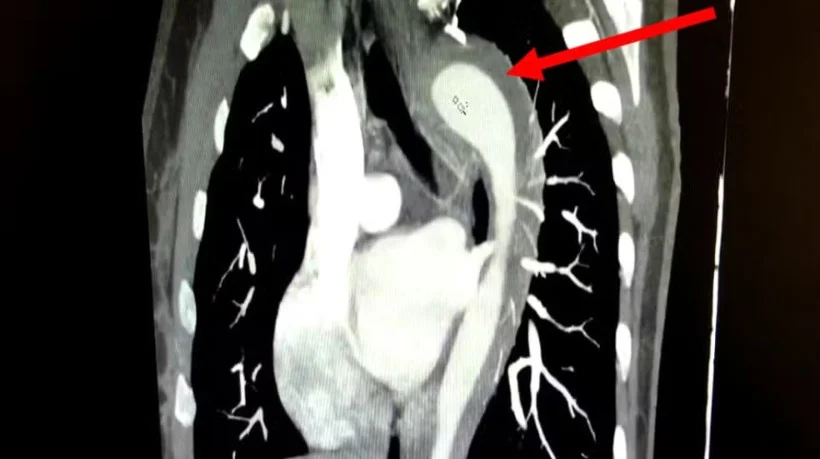

Ruptura de aorta após orgasmo: mulher de 45 anos sobrevive a caso raro

Paciente chegou à emergência com queixas de dores toráxicas. Segundo os médicos que atenderam o caso, o histórico médico incluía hipertensão, não tratada há um ano, e tabagismo há 17 anos